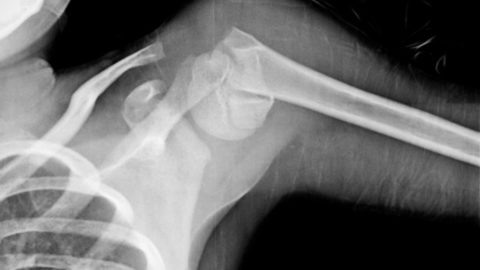

Рентгенограмма перелома плечевого сустава

Закрытые и открытые переломы плечевого сустава сопровождаются повреждениями  мягких тканей: клетчатки, мышцев, сосудов, нервов, кожи. В месте травмы возникают болевые синдромы, припухлости, отеки, изменяется конфигурация костей, нарушается двигательная функция.

При сращивании костной ткани в результате образования костной мозоли одновременно с лечением начинают восстановление плечевого сустава после перелома.  Оно состоит из иммобилизационного, функционального и тренировочного этапов.

Основной целью реабилитации является исключение боли, возвращение необходимой амплитуды движения в суставе за счет правильного сопоставления отломков костей, активизации процессов регенерации и адаптации.